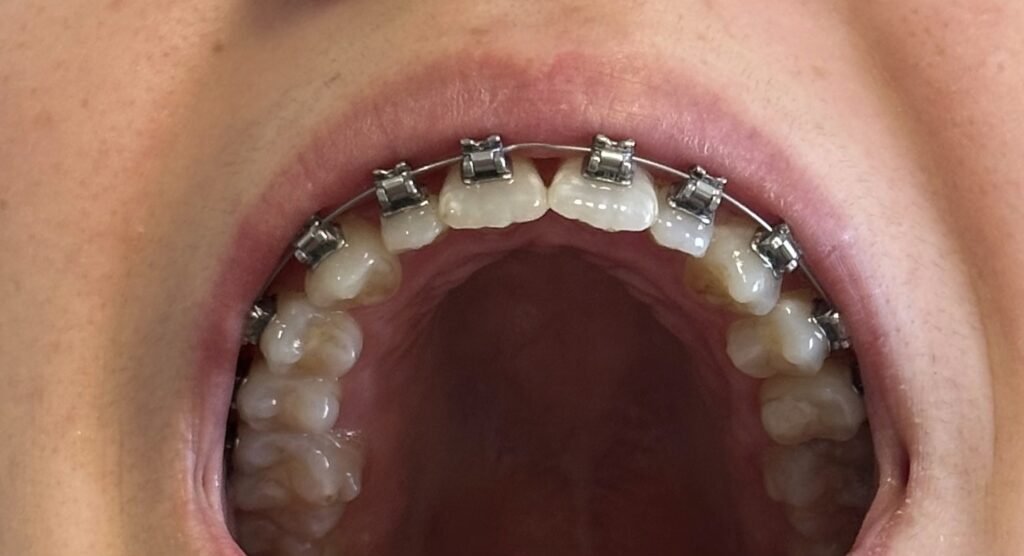

Antes, durante e depois da expansão maxilar cirurgicamente assistida